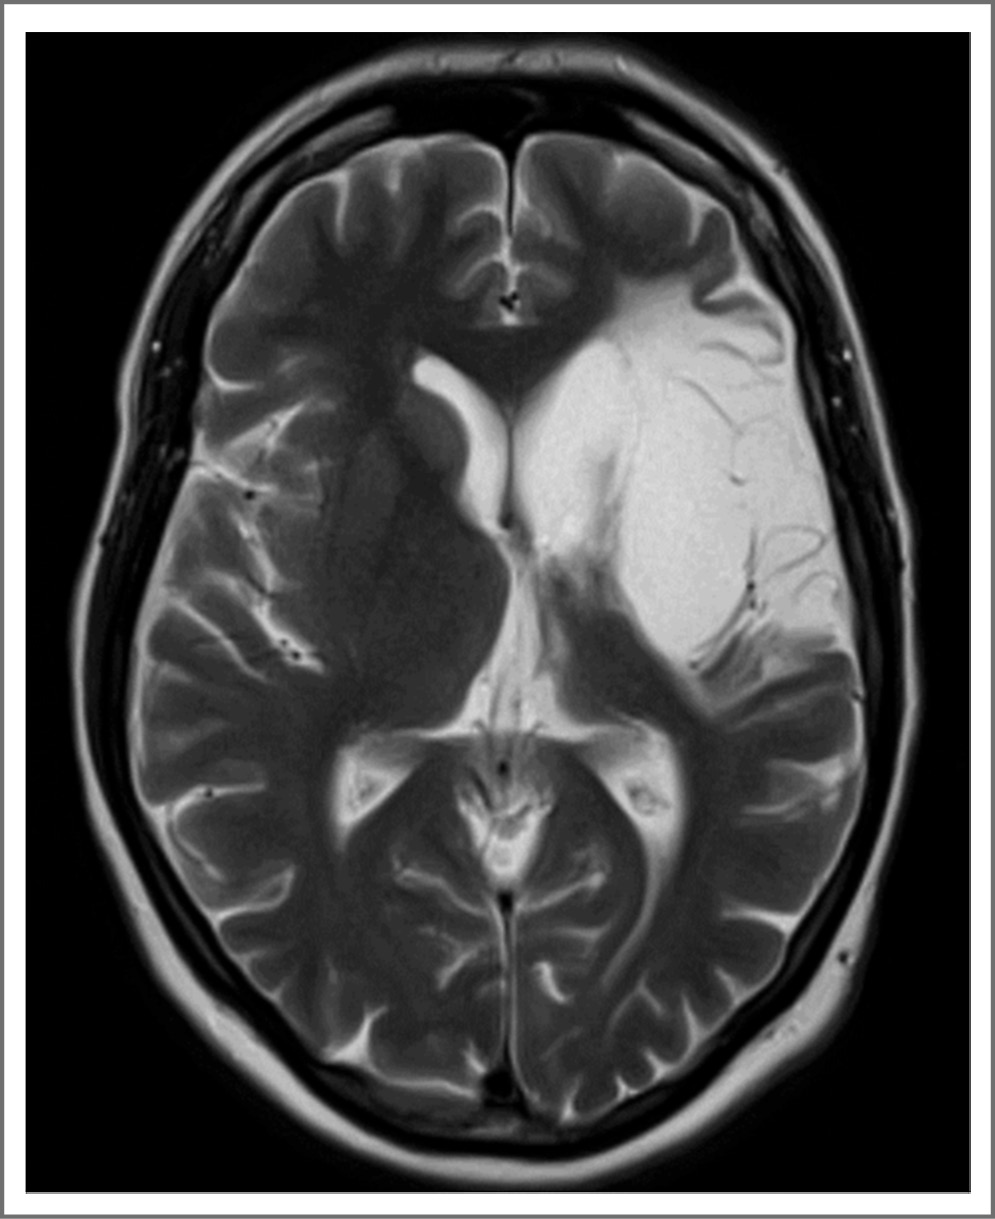

Обращает на себя внимание возникновение очаговой неврологической симптоматики на фоне острой респираторной инфекции с изнуряющим кашлем; других провоцирующих факторов установить не удалось. Индекс массы тела – в пределах нормальных значений, курения и других вредных привычек, а также артериальной гипертензии не зарегистрировано. Диагноз подтвержден данными магнитно- резонансной томографии (МРТ; рис. 2). В стационаре выполнено обследование, направленное на поиск наиболее вероятной причины ИИ. Значимых отклонений от нормы электрокардиографией (ЭКГ) не установлено. При суточном мониторировании ЭКГ определялся синусовый ритм. При стандартном лабораторном обследовании патологических изменений, в том числе дислипидемии, гипергликемии, снижения функции почек, электролитного дисбаланса, не выявлено. По данным эхокардиографического исследования расширения полостей сердца и наличия в них тромбов, а также изменения клапанов сердца не зафиксировано. По данным дуплексного сканирования и ангиографии с применением мультиспиральной компьютерной томографии гемодинамически значимого стенозирования брахиоцефальных артерий не установлено, аномалии интракраниальных артерий отсутствуют. Таким образом, учитывая наличие обширного ишемического очага корковой локализации по данным МРТ и отсутствие явных причин, можно говорить о перенесенном в возрасте 38 лет эмболическом инсульте из неустановленного источника. Напомним, что стандартом вторичной профилактики ESUS является монотерапия антиагрегантом [3, 5, 8], обычно речь идет об ацетилсалициловой кислоте (АСК), и именно этот препарат и назначили пациентке после инсульта.

Рис. 2. МРТ головного мозга через 6 мес после развития ИИ. Корково-подкорковый инфаркт в бассейне левой средней мозговой артерии (режим Т2: гиперинтенсивный сигнал в бассейне левой средней мозговой артерии).